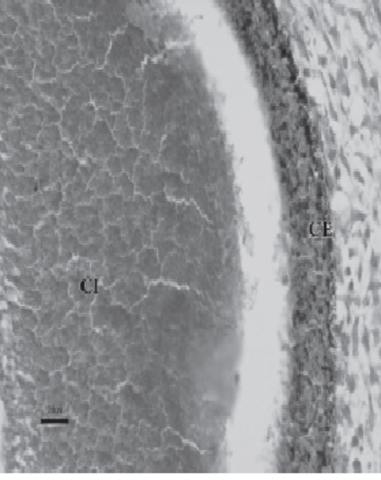

La cúpula óptica está compuesta por 2 hojas o capas:

1. Interna, poliestratificada, que dará lugar a la retina

neural.

2. Externa, formada por 2-3 capas seudoestratificadas,

esbozo de la lámina pigmentaria.

Bajo la influencia del cristalino en desarrollo, la capa u hoja interna, futura retina neural, prolifera y da lugar a un neuroepitelio grueso que se diferenciará en retina neurosensorial. Esta zona contendrá los fotorreceptores y los cuerpos celulares de las neuronas.

Las células de la capa externa o lámina pigmentaria de la retina no se diferencian en neuronas durante el período prenatal, pero en la vida posnatal algunas de estas células mantienen propiedades de células madre y pueden diferenciarse en múltiples tipos de células. Se considera que la melanina, o algún producto asociado, regula el desarrollo de las capas neurales.